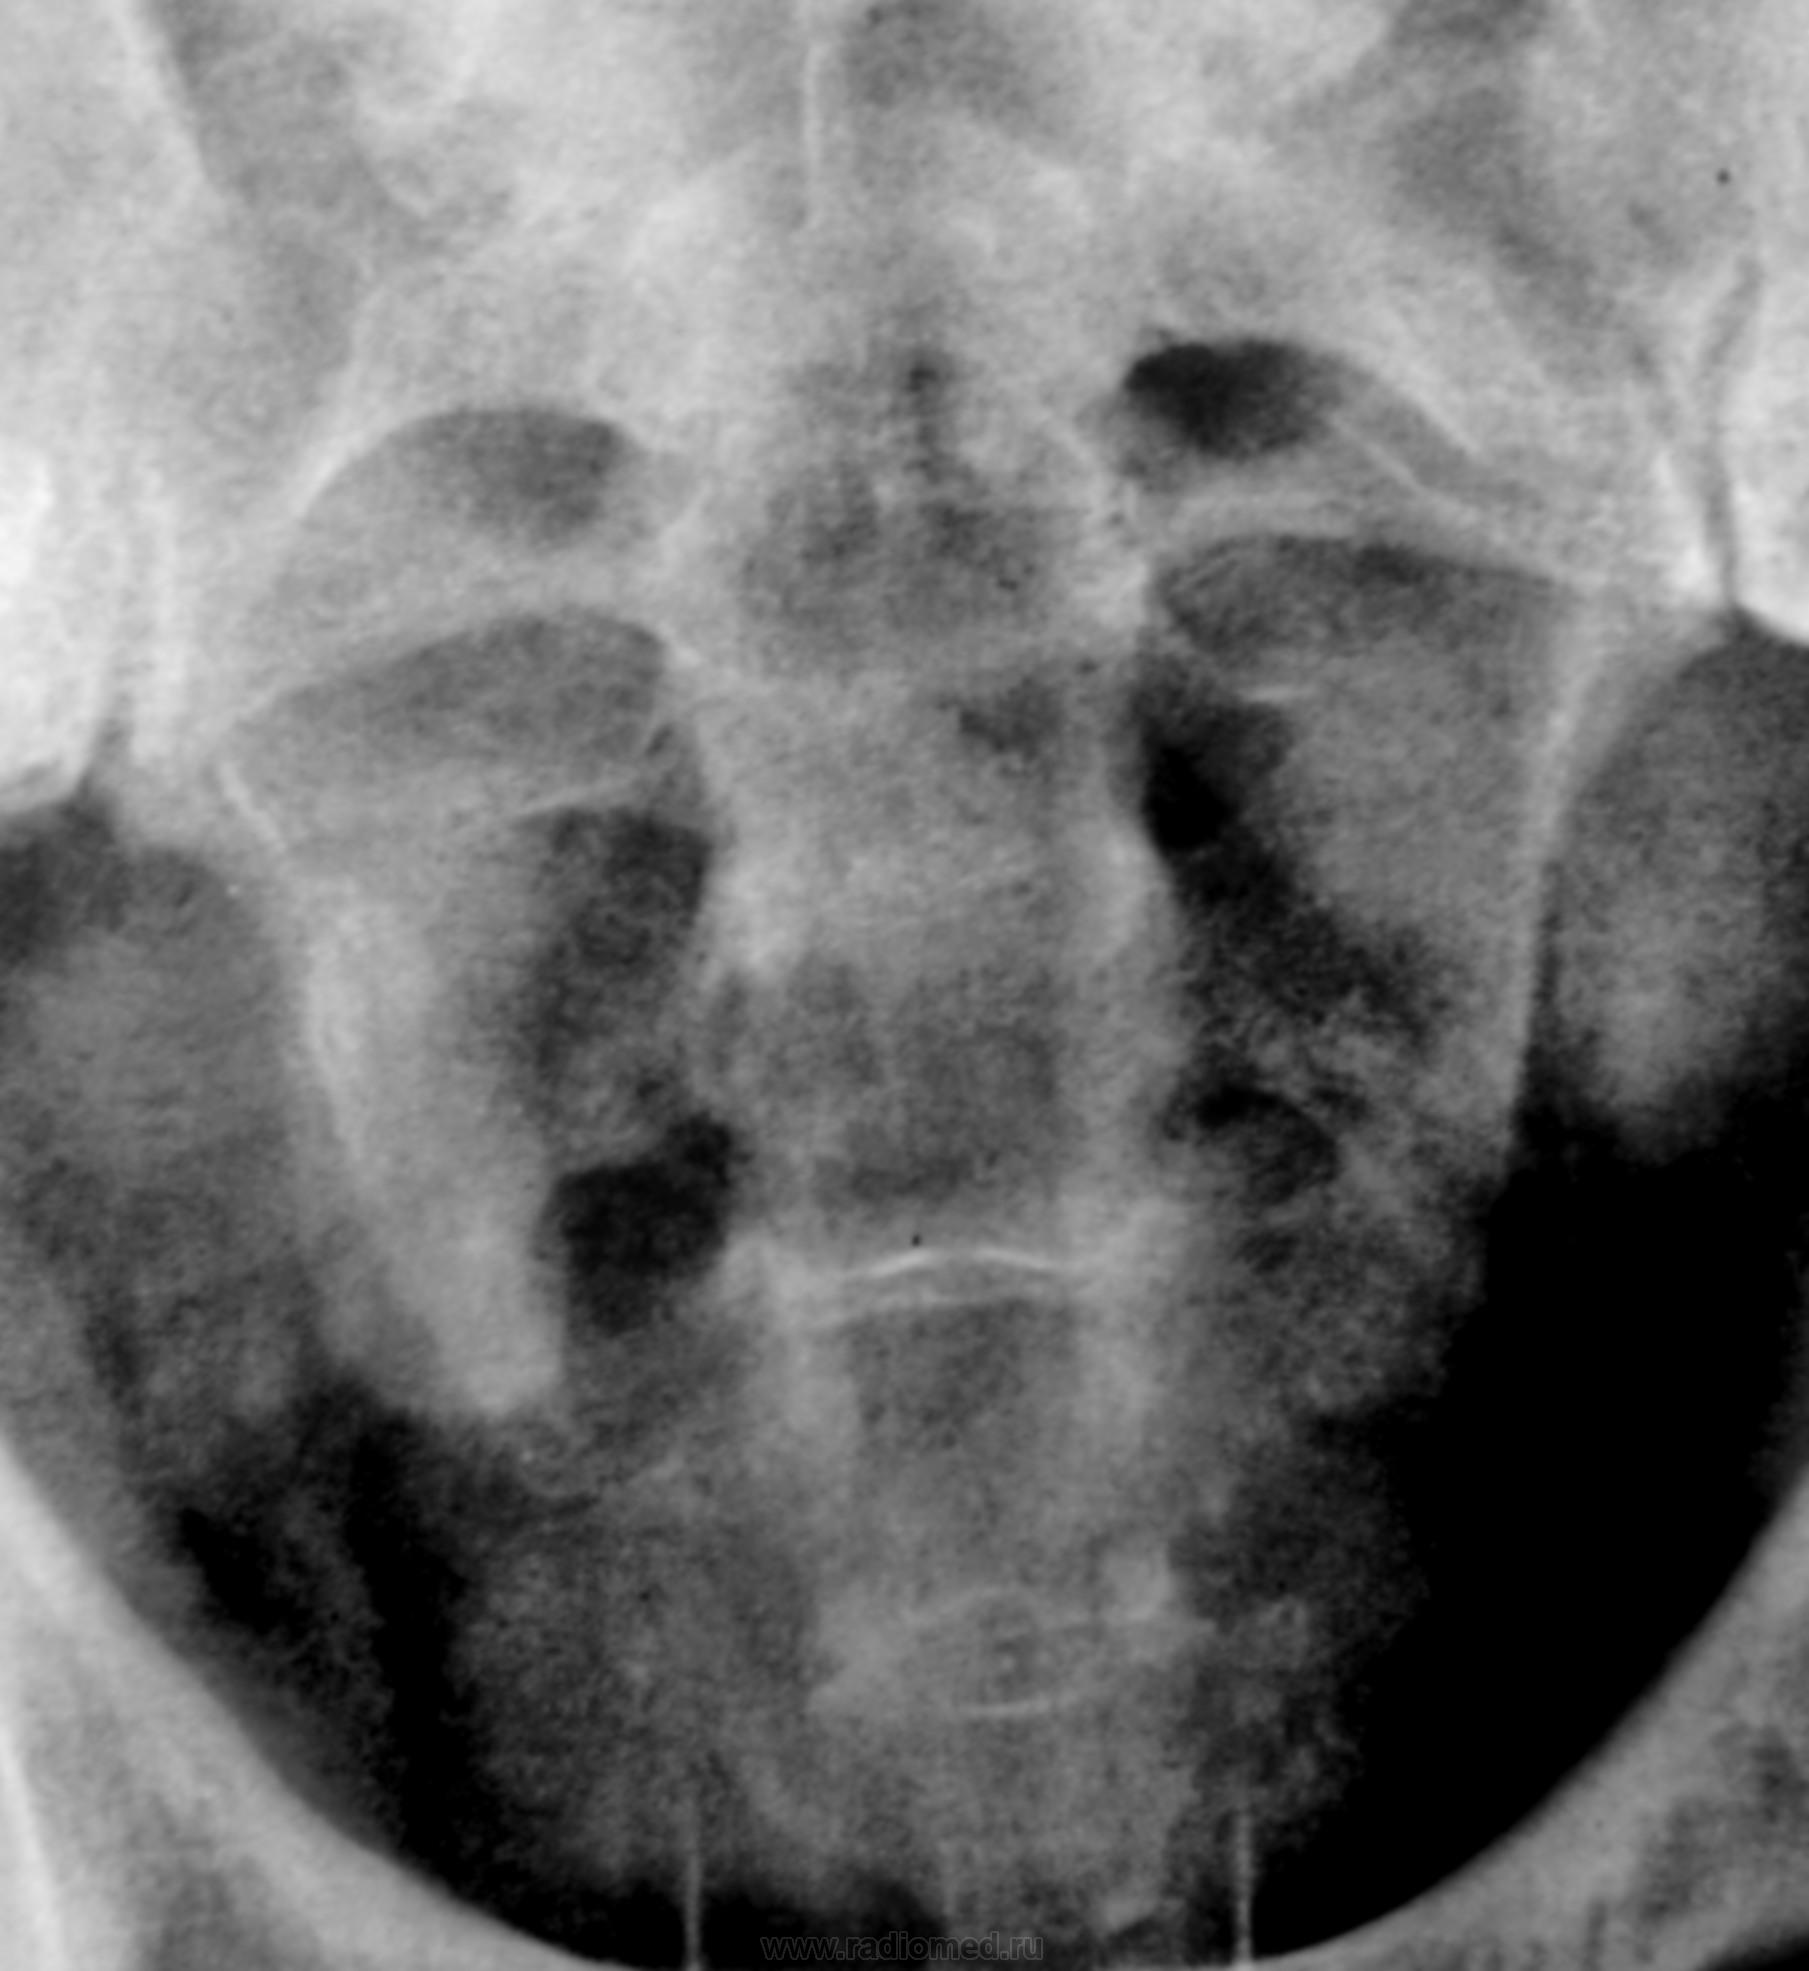

Пациент с диагнозом "МКБ" направлен на обзорную рентгенографию почек и мочевыводящих путей.

Пациент с диагнозом "МКБ" направлен на обзорную рентгенографию

Внутривенная урография.

На мой взгляд дополнительная интенсивная тень лежит за контуром почки. В проекции Желчного пузыря. Так что желчекаменная болезнь? Рекомендованно УЗИ печени и желчного пузыря.

Да с камнем желчного то все понятно...но вот тень в проекции н\трети правого мочеточника ....весьма необычна...вопрос - куда ее "пристроить"?))))

Я не про "утверждаю", Боже спаси, для мочеточника тень очень больших размеров, хотя расположена вдоль его проекционной оси, но здесь же проекция крупных сосудов, стенты сейчас могут быть всякими разными, а потом-в малом тазу не только у женщин, но и мужчин хватает всякого, что может обызвествляться. А верхняя тень-типично для желчного пузыря.

Да, камешек для желчного типичный.

А тень в дистальной трети мочеточника действительно "фердиперсовая"...

Признавайтесь, куда делась средняя треть правого мочеточника? Ее как-будто ножом отрезали под линейку, а ниже-сплошное безобразие! "ЧТО" может как обезобразить орган-банальная МКБ с частичной обтурацией просвета или опухоль? А в пузыре тоже камни?

Вы правы, камней не много, их - до "фига"...

Отчего же не смущает?))) смущает...она и есть первопричиной образования ТАКОГО камня в мочеточнике, теперь об этом можно сказать с уверенностью, ее генез - выраженое увеличение размеров простаты.